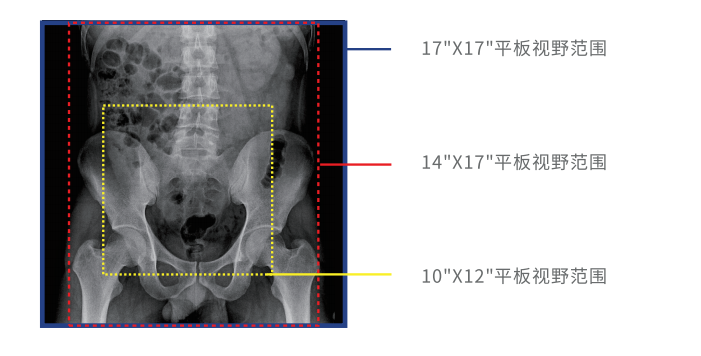

大幅面高清成像

動(dòng)態(tài)DR采用17 英寸×17 英寸方形動(dòng)態(tài)成像,臨床操作醫(yī)生可以在一個(gè)大幅面下觀察診斷,當(dāng)看到病變部位時(shí),配合實(shí)時(shí)點(diǎn)片技術(shù),能夠很好地捕捉到病變點(diǎn),也大大縮短了檢查時(shí)間,與圓形成像的傳統(tǒng)胃腸機(jī)相比在臨床上具有巨大優(yōu)勢。